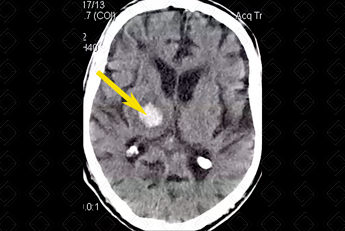

Texto alternativo para a imagem Figura 2. Créditos: Dra. Elazir Mota - Rio de Janeiro/RJ

Descrição da figura 2: Imagem hiperdensa, compatível com sangramento no tálamo direito (seta amarela).

• Hemorragia hipertensiva: Hematoma focal agudo ou micro-hemorragias. Localizações mais comuns: putâmen e cápsula externa (mais comuns, cerca de 60-65% dos casos). Outras localizações típicas são tálamo, centro semioval, cerebelo e ponte (f iguras 1 e 2);